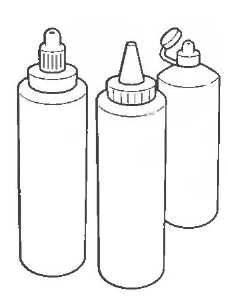

Лучшими акустическими связывающими агентами являются водорастворимые гели. Многие из них производятся промышленным путем, но они стоят дорого, их временами трудно получить. Нет необходимости использования специального связывающего агента для отдельного вида оборудования, даже если производители настаивают на этом. Специальные связывающие агенты не дают преимущества в получении изображения. Формула связывающего агента для аппаратуры общего назначения для любого датчика приведена на с. 45.

Связывающий агент лучше использовать в пластиковых бутылочках, из которых гель выдавливается на кожу пациента. Это позволяет избежать излишнего загрязнения. Пригодна любая пластиковая сжимаемая бутылочка, но она должна быть полностью чистой и сухой перед тем, как будет заполнена гелем. Если имеется открытая рана, повреждение кожи или другой риск инфицирования, покройте датчик или кожу пластиком; поместите связывающий агент по обе стороны пластика. Датчик необходимо очищать после каждого пациента.